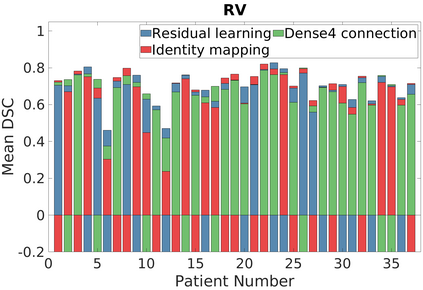

Deep Convolutional Neural Networks (DCNNs) are used extensively in biomedical image segmentation. However, current DCNNs usually use down sampling layers for increasing the receptive field and gaining abstract semantic information. These down sampling layers decrease the spatial dimension of feature maps, which can be detrimental to semantic image segmentation. Atrous convolution is an alternative for the down sampling layer. It increases the receptive field whilst maintains the spatial dimension of feature maps. In this paper, a method for effective atrous rate setting is proposed to achieve the largest and fully-covered receptive field with a minimum number of atrous convolutional layers. Furthermore, different atrous blocks, shortcut connections and normalization methods are explored to select the optimal network structure setting. These lead to a new and full-scale DCNN - Atrous Convolutional Neural Network (ACNN), which incorporates cascaded atrous II-blocks, residual learning and Fine Group Normalization (FGN). Application results of the proposed ACNN to Magnetic Resonance Imaging (MRI) and Computed Tomography (CT) image segmentation demonstrate that the proposed ACNN can achieve comparable segmentation Dice Similarity Coefficients (DSCs) to U-Net, optimized U-Net and hybrid network, but with significantly reduced trainable parameters due to the use of full-scale feature maps and therefore computationally is much more efficient for both the training and inference.